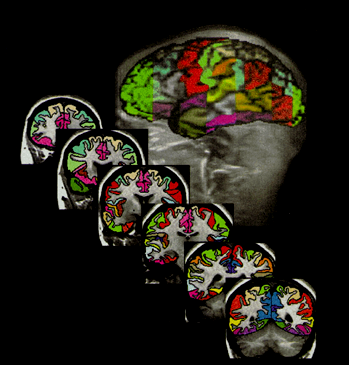

Use multi-modal imaging to characterize sex differences in neurobiology, ANS, immune, and steroid hormone physiology & neurovascular dysfunction associated with stress response circuitry deficits in recurrent depression vs. healthy controls.